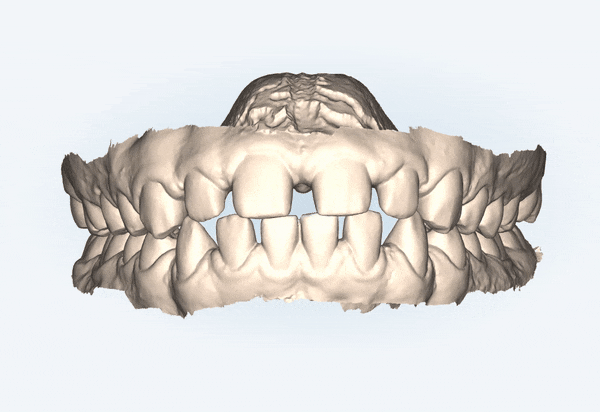

1st Clincheck

교정기간 23/7~24/6

잠실새내인비절라인 유펜바른치과의

첫번째 클린체크를 보시면

인비절라인라이트 케이스의

14개의 장치로 완성도 높은 치료 결과를

보여주었는데요^^

인비절라인 단 14개의 장치로

치아사이의 공간을 닫고

튀어나와있던 앞니의 각도를 개선시켜주었습니다~!